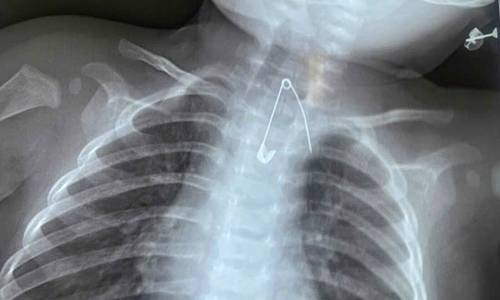

Safety pin lodged in 7-month-old baby's esophagus VnExpress A 7-month-old boy, suffering from a two-day fever and persistent cough, was found by doctors to have a safety pin lodged in his esophagus, dangerously close to his aorta.